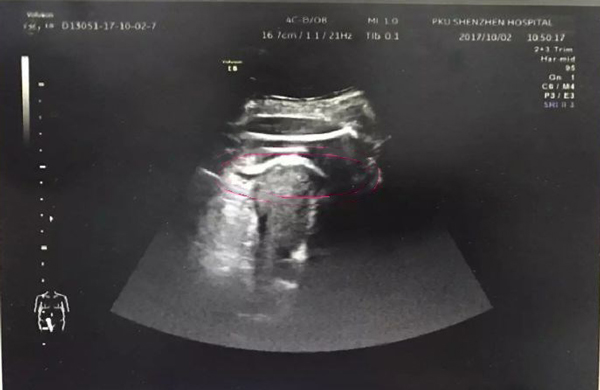

Kết quả siêu âm cho thấy chân của thai nhi đã phá vỡ tử cung, thò sang khoang bụng, đùi bị mắc kẹt tại thành tử cung. Cả sản phụ và thai nhi đang đối mặt với nguy hiểm vì mẹ có thể bị nhiễm trùng, xuất huyết còn con dễ bị ngạt khí.

Hình ảnh siêu âm cho thấy phần đùi của em bé bị mắc kẹt tại thành tử cung.